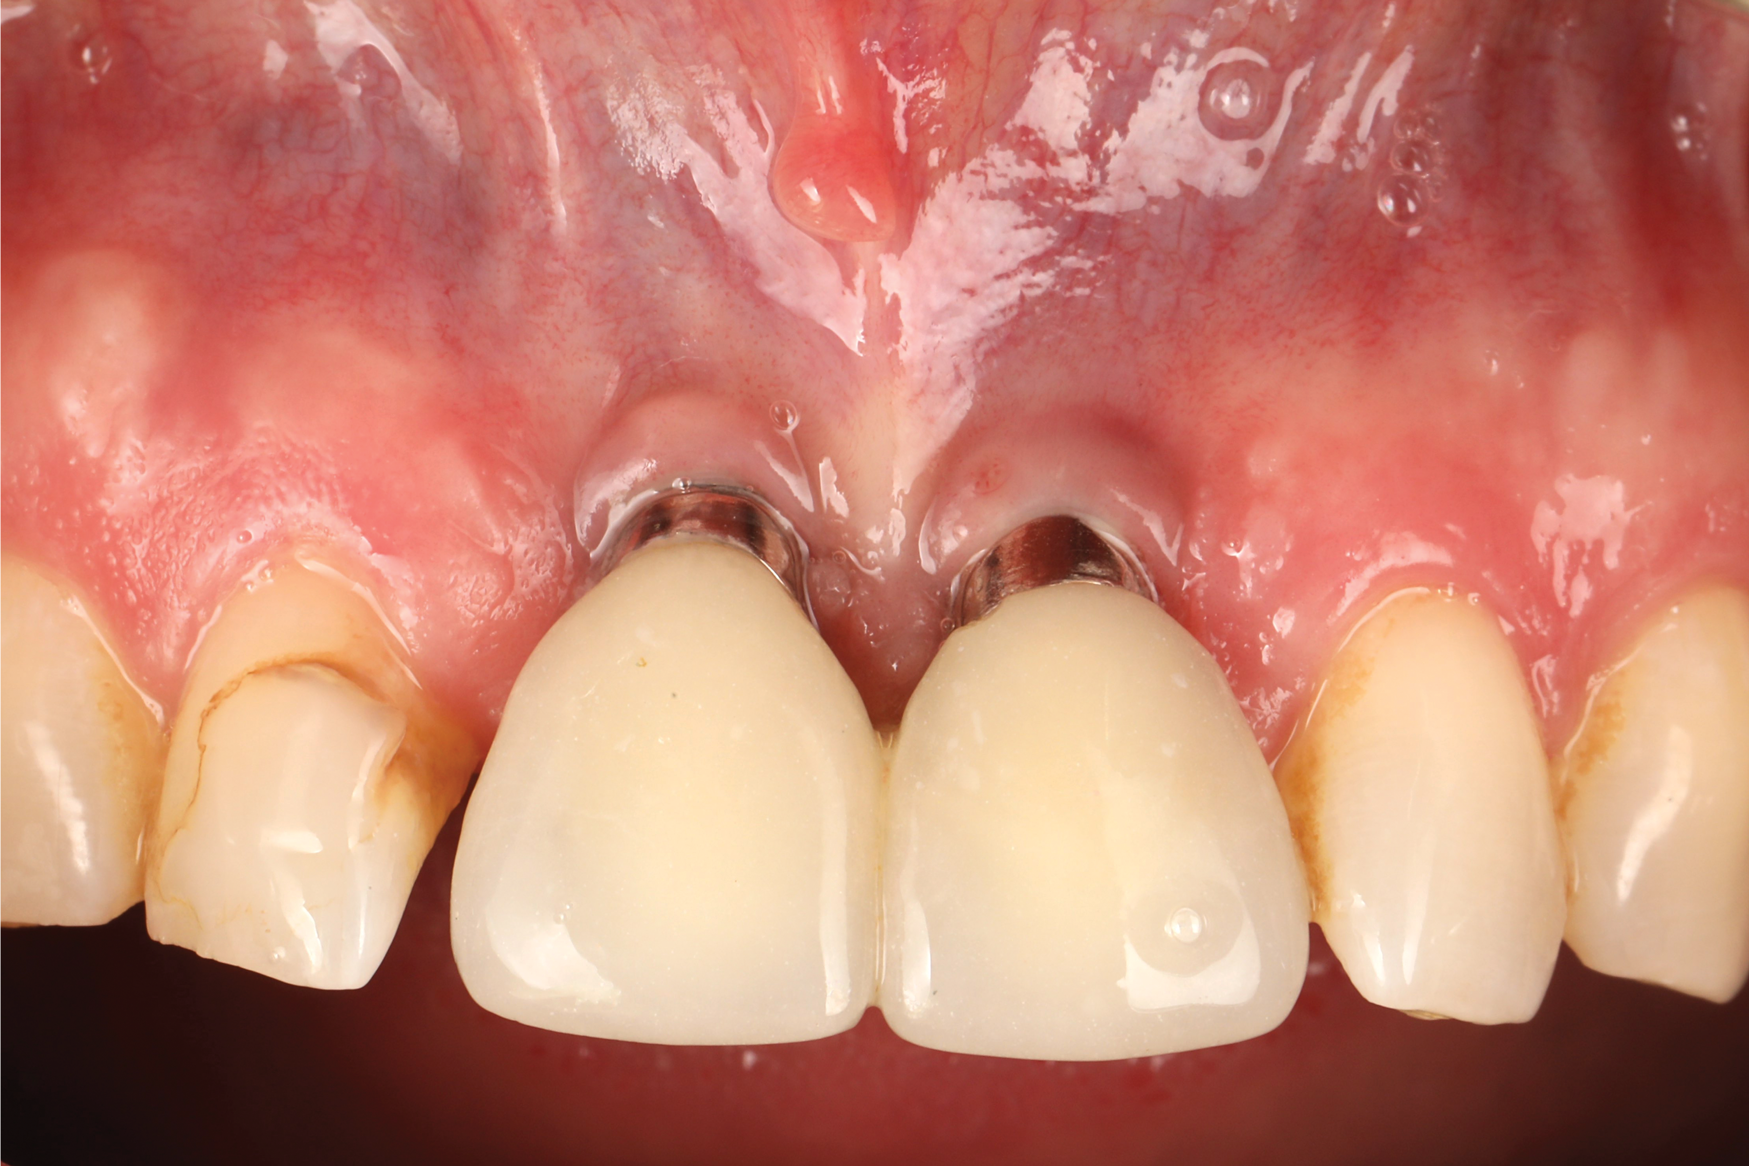

Fig 2. Baseline periapical x-ray.

Figure 2

A 46-year-old systemically and periodontally healthy woman presented to the Graduate Periodontics Clinic at the University of Michigan School of Dentistry with the chief complaint of poor esthetics of her smile due to two dental implants (Nos. 8 and 9) showing their metal components (Figure 1). The patient reported that the implants had been placed 15 to 20 years previously after an accident. Clinical examination revealed that the implants had probing depths within 3 mm (facial probing depth of 3-2-3 mm for implant No. 8 and 2-2-2 mm for implant No. 9), no bleeding on probing, and no suppuration; the implants were therefore diagnosed as healthy (Figure 1 and Figure 2). The papilla between the two implants was deficient on the buccal aspect. The implants were buccally positioned, and a substantial lack of soft-tissue volume was noted.